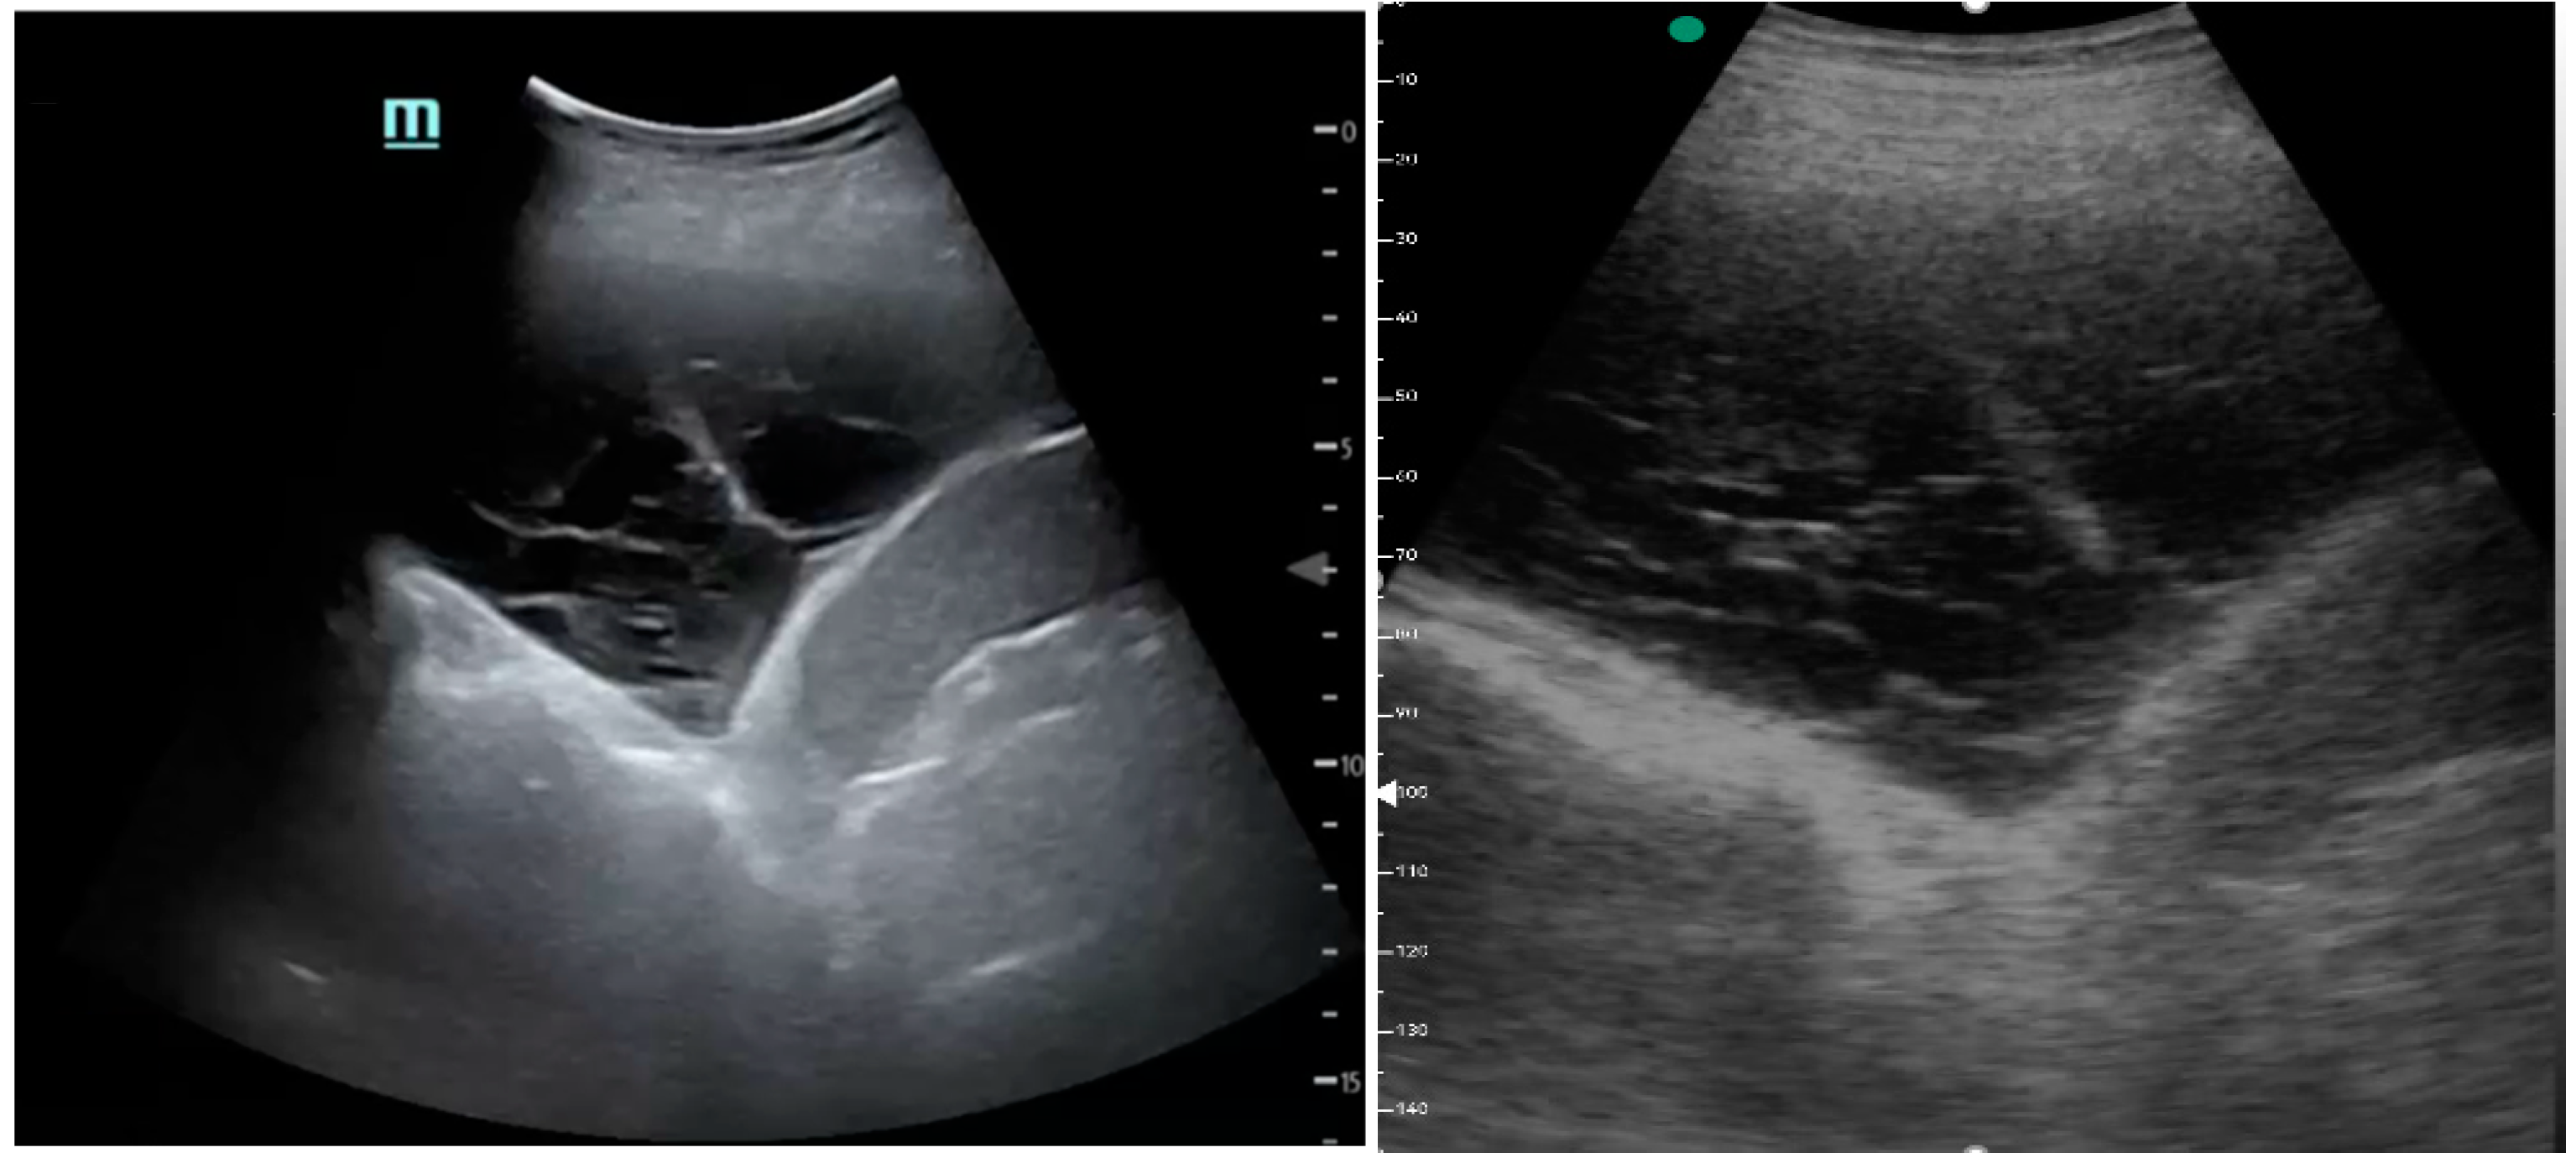

Figure 1, Figure 2 and Figure 3 exhibit characteristic examples of ultrasound still images from the videos captured via a standard ultrasound (left side) and portable handheld device (right side). Quality may slightly differ from that of the videos as these are still images.

Figure 3. Simple pleural effusion with atelectasis.